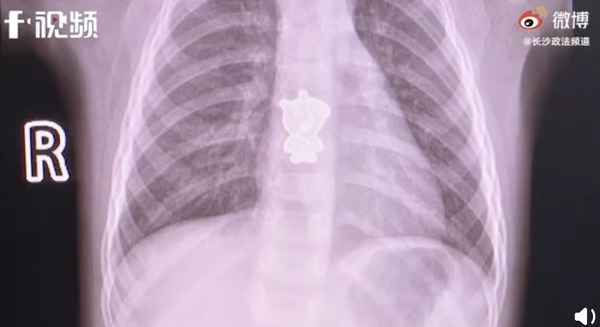

根據內地媒體《新浪新聞》報導,中國湖南長沙一名一歲女童早上起床後開始不斷哭鬧,咳嗽亦帶有血絲,家屬見狀趕緊送她到醫院。經檢查後,醫生在電腦斷層掃描(CT Scan)結果發現,女孩食道中下段有一個金屬「Peppa Pig」陰影。幸好進行手術後,該隻「Peppa Pig」已被順利取出。

Photo from 《新浪新聞》